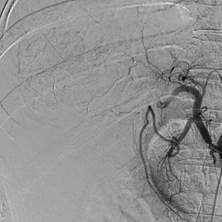

患者被送入导管室后,郑胜与放射科主治医师苏维杰第一时间开始经股动脉肝动脉造影与栓塞术。术中用碘化油及明胶海绵颗粒对出血动脉进行了栓塞,成功止血。

术后

郑胜介绍,相较于急诊开腹止血手术,介入栓塞术具有创伤小、恢复快、并发症少等优势,能最大限度地保护肝功能。

同时,血管造影能进一步明确肿块大小、范围及血管情况,为接下来的治疗提供依据。